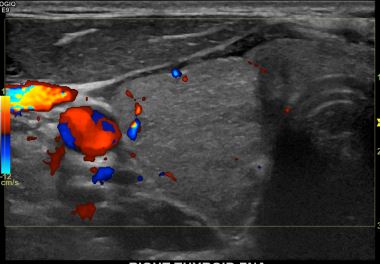

상기환자  외부검사이상소견으로 내원하신 40대 초반 남성분으로 의심스러운 갑상선 우엽결절 세포검사진행후 갑상선암으로 진단되었습니다